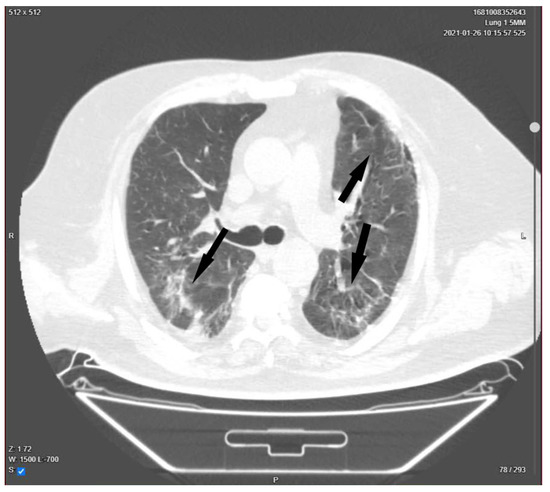

The Successful Recovery of a Critically Ill COVID-19 Patient, Following the Combination of Therapeutic Plasma Exchange and Convalescent Plasma Transfusion: A Case Report

With an intricate symptom pattern involving a dysregulated host response to infection, the severe acute respiratory syndrome coronavirus 2 (SARS-CoV-2) can cause severe inflammation and cytokine storms, acute respiratory distress syndrome, coagulopathy, multi-organ failure, and finally death. The uniqueness of this case report [...] Read more.

With an intricate symptom pattern involving a dysregulated host response to infection, the severe acute respiratory syndrome coronavirus 2 (SARS-CoV-2) can cause severe inflammation and cytokine storms, acute respiratory distress syndrome, coagulopathy, multi-organ failure, and finally death. The uniqueness of this case report lies in the nature of the therapeutic intervention performed. While numerous studies are available on both the use of therapeutic plasma exchange in coronavirus disease 2019 (COVID-19) patients and convalescent plasma transfusion as separate treatment methods, there is very little information regarding the combination of these procedures. We present the case of a 52-year-old male, unvaccinated for COVID-19, who tested positive on reverse transcriptase polymerase chain reaction for SARS-CoV-2 for the first time and presented in the emergency room with fever, chills, severe cough, tachypnea, tachycardia, and dyspnea that started two days before presentation. Upon rapid assessment, the patient showed signs of acute respiratory failure, so it was decided to transfer the patient to the intensive care unit, COVID-19 ward, after preliminary radiological examination. For the next 24 days, the patient was stationed in the intensive care unit, where he was closely monitored and treated. Invasive mechanical ventilation was required following the initial worsening of his respiratory status. We performed therapeutic plasma exchange on the first day of his stay in the intensive care unit, and immediately after the procedure, the patient was transfused with 500 mL of convalescent plasma from healthy donors. The patient’s condition improved over the next few days, which led to the cessation of mechanical ventilation and, after treating the superinfection, the patient was discharged home, making a full recovery. The early initiation of therapeutic plasma exchange followed by transfusion of convalescent plasma in severe and critical forms of COVID-19 may reduce the risk of the progression of the disease and ultimately reduce the risk of negative outcomes in a selected group of patients. Full article